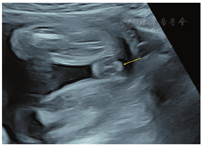

孕妇,21岁,孕4产0,孕27周。因外院羊水染色体核型分析提示47,XXX来我院行胎儿系统超声筛查。超声检查显示:胎儿生物学测量相当于孕23周+,胎儿面中部凹陷,鼻部短小,鼻梁低平,尾椎多个椎体融合、回声增强,左侧肱骨两端干骺端及双侧股骨近端干骺端可测及数个点状强回声斑(图1);双手掌及双足板短小,以指(趾)端明显,双手掌及双足板多个骨性结构短小、部分骨性结构未能显示(图2);胎儿阴蒂肥大(图3)。超声诊断:①宫内妊娠,中孕单活胎,相当于孕23周+;②胎儿面中部畸形、尾椎畸形、双侧股骨近端及肱骨两端点状强回声斑、双手及双足发育不良——Binder综合征可能;③胎儿外生殖器异常——阴蒂肥大;④胎儿宫内生长迟缓(intrauterine growth restriction,IUGR)。孕妇无华法林服用史等特殊病史,无酗酒史,维生素K依赖性凝血因子、凝血酶原时间正常。

本病例产前超声提示胎儿阴蒂肥大,引产后证实。胎儿阴蒂肥大主要考虑以下原因:①妊娠期母体雄激素水平增高;②胎儿先天性肾上腺皮质增生症;③胎儿卵巢肿瘤;④胎儿性染色体数目异常;⑤特发性(原因不明)[6]。孕妇无多囊卵巢综合征及卵巢肿瘤病史,雄激素水平正常,排除胎儿阴蒂肥大由妊娠期母体高雄激素引起。高通量测序行CYP21A2基因检测提示阴性,排除了胎儿先天性肾上腺皮质增生症。超声扫查胎儿盆腹腔未见明显肿块声像,胎儿阴蒂肥大不考虑由胎儿卵巢肿瘤引起。本病例羊水染色体核型为47,XXX,为超雌综合征,综合考虑胎儿阴蒂肥大可能是由胎儿性染色数目异常引起,胎儿性染色数目异常、基因表达异常导致卵巢发育不全、下丘脑-垂体-卵巢轴功能异常,从而引起雄激素产生过量。因此,对于性染色体异常的胎儿需注意仔细扫查外生殖器,观察有无外生殖器畸形,以减少误诊或漏诊。Binder综合征染色体核型多为正常,而本例Binder综合征合并性染色数目异常,至于Binder综合征的发病机制与性染色体异常有无关系,目前鲜见相关文献报道。